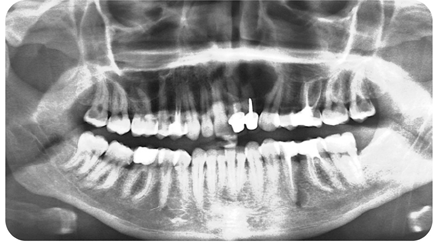

Difficulties of Endodontics Access Treatment and its Challenges: A Case Series

El Kharroubi Soukaina, Dhoum Sara, Doumari Bouchra, Drouri Sofia and Laslami Kaoutar. 22(8): 01-12.